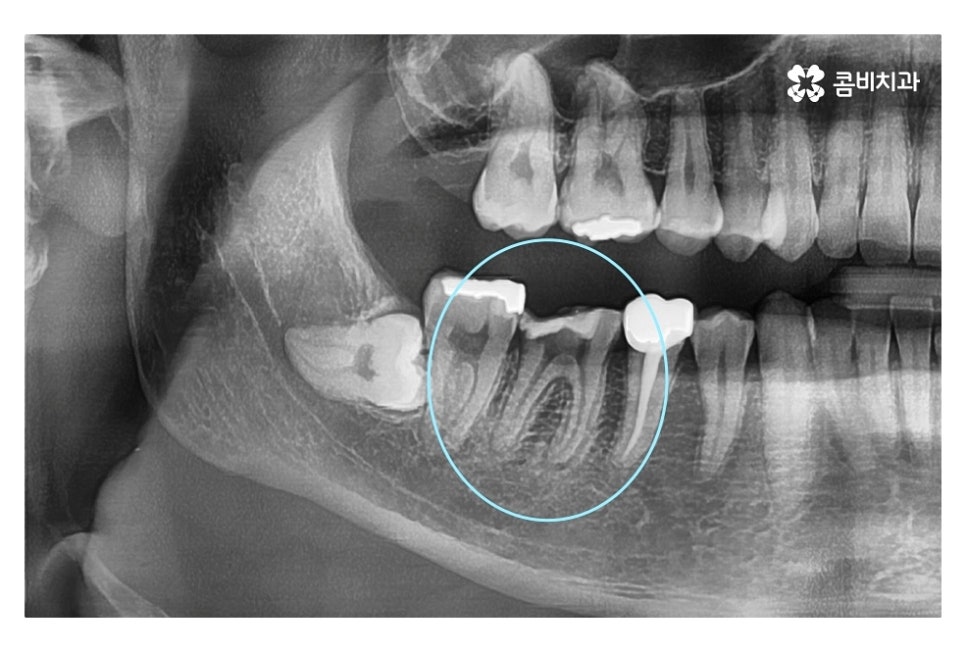

같은 환자분의 사진인데 좌측 치아의 경우 신경치료 후 크라운으로

마무리를 했지만 우측 어금니의 경우 치아의 대부분이

손상이 되어 결국 발치 후 임플란트를 하게 된 사례라고 할 수 있는데요.